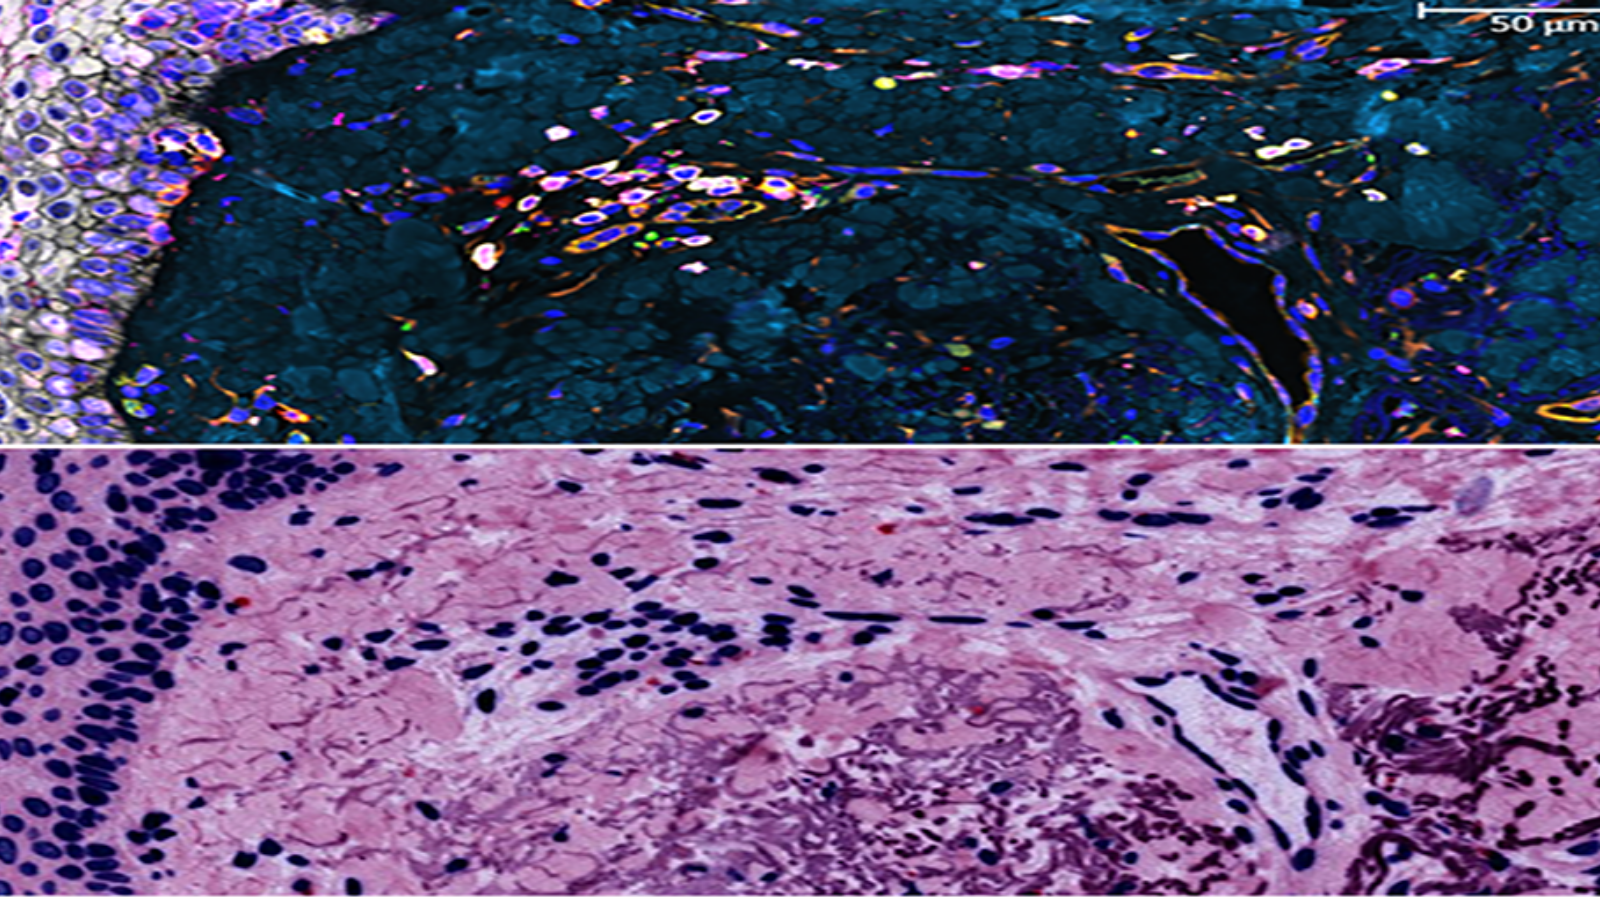

The lining of the uterus & fetal cells within & around maternal spiral arteries, courtesy of Dr. Michael Angelo at Stanford

Proteins in the epidermis, the outermost skin layer, courtesy of Dr. Fiona Ginty at GE Research

Image shows 9 markers of a follicle in skin, courtesy of Dr. Fiona Ginty at GE Research